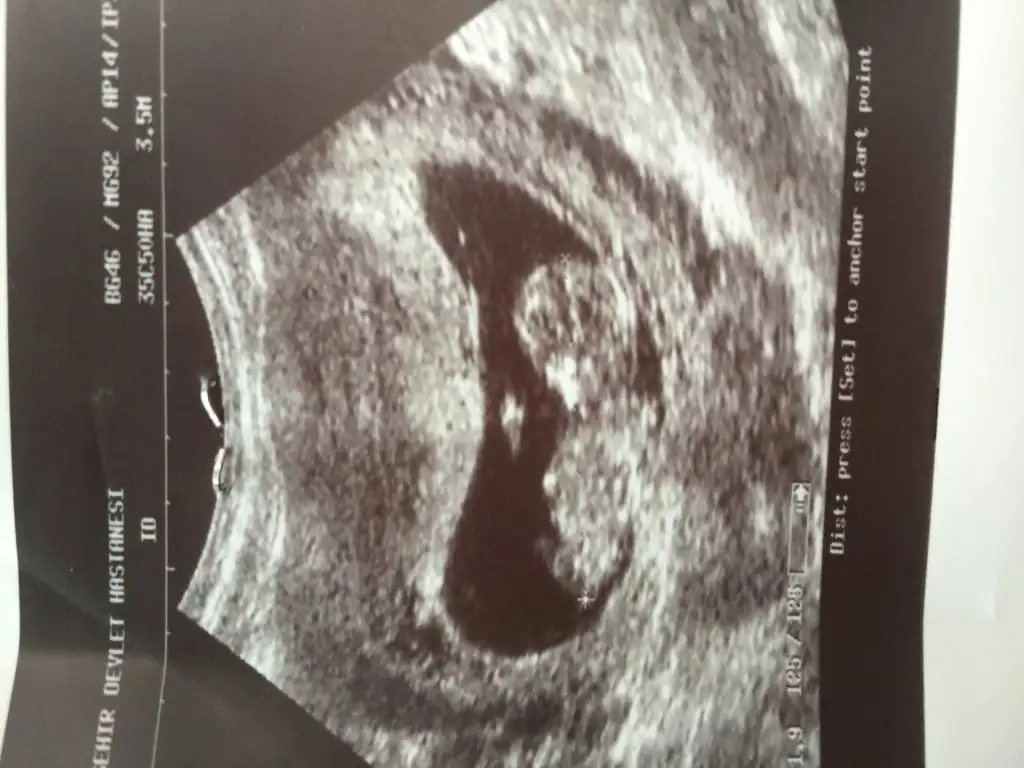

kızlar, konunun basında yazana göre sağda olursa kız, solda olursa erkek oluyormus :=) yanı ben konuda yazana göre söyluyorum

hee bır de guya kesenın seklı fasulye gıbı olursa erkekmıs rivayetlere göre :D